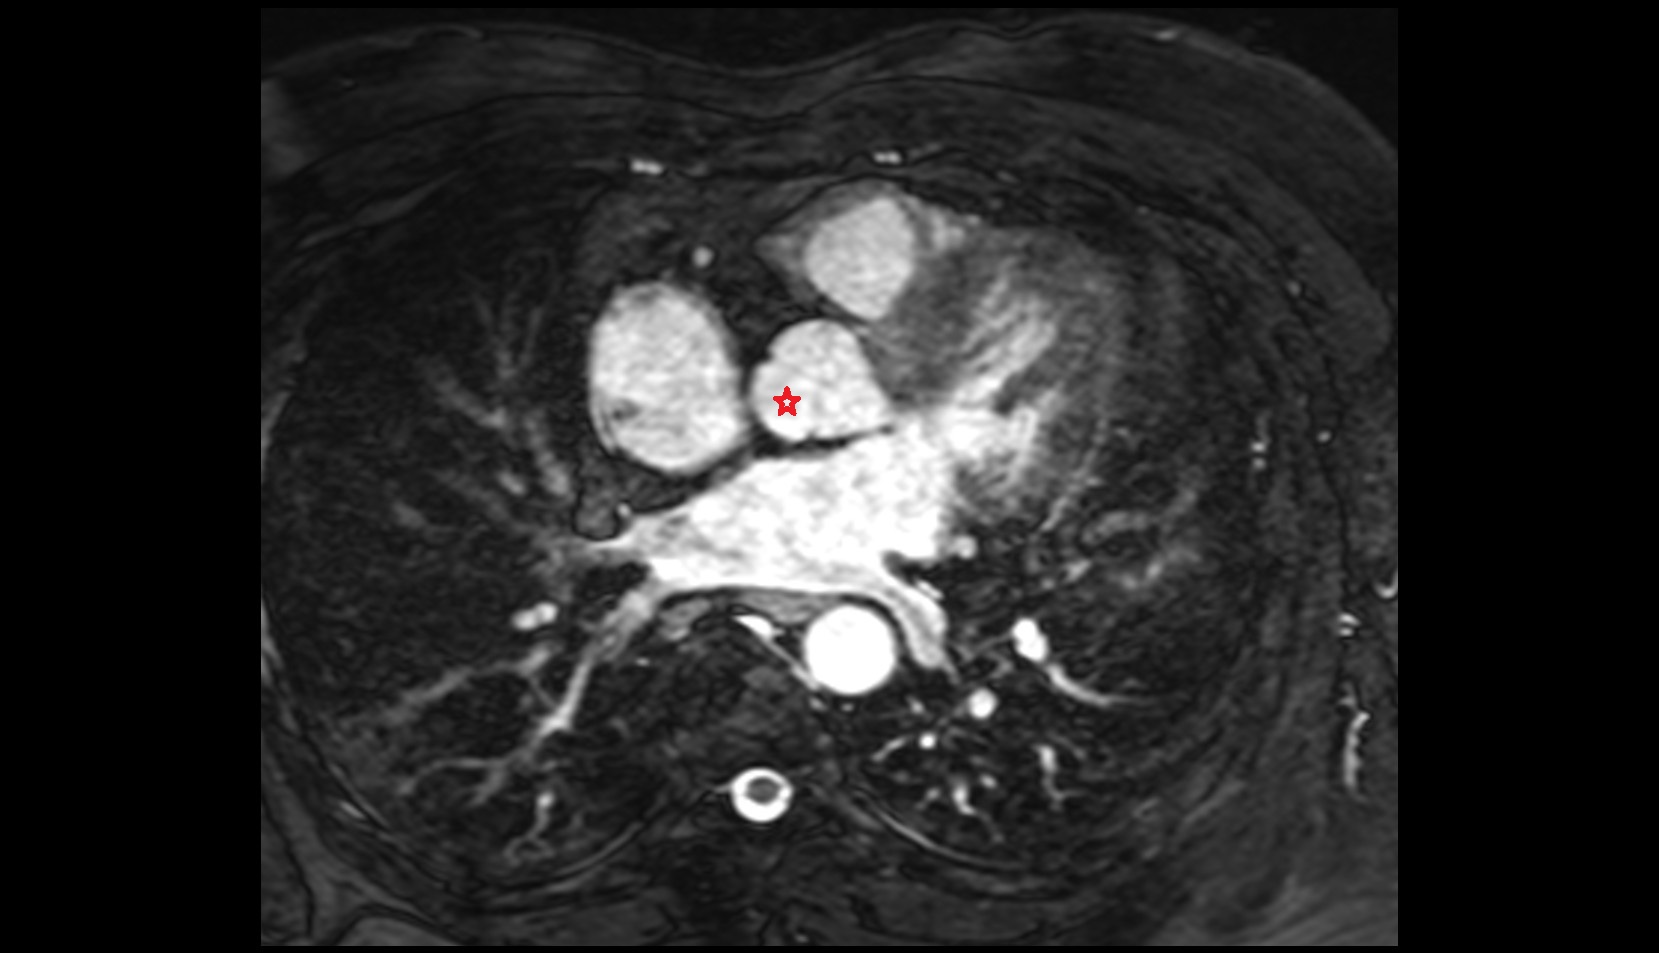

- Left main coronary artery (LMCA)

- Left anterior descending artery (LAD)

- Circumflex artery (LCx)

- Right coronary artery (RCA)